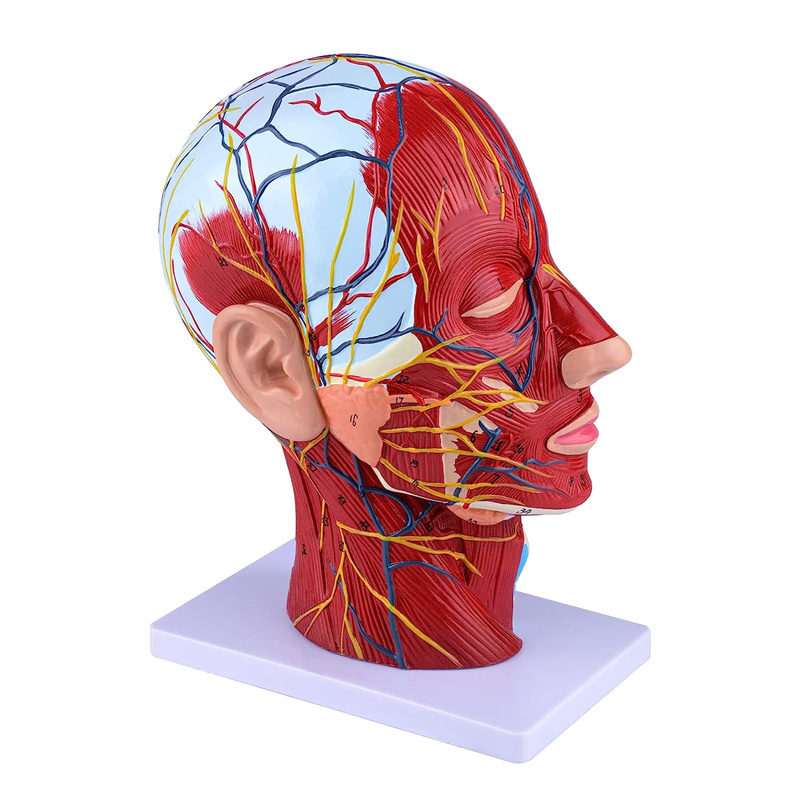

| Karatteristiċi | Il-mudell juri l-morfoloġija lokali tal-ġnub ta 'ġewwa u ta' barra tas-sezzjoni sagittali medjana tar-ras u tal-għonq, kif ukoll l-istrutturi tal-bastimenti tad-demm u n-nervituri, u hemm 84 partijiet li jindikaw sinjali b'kollox. |

【Mudell tal-muskolu newrovaskulari superfiċjali】 Dettaljat ħafna, numri mmarkati, li jistgħu jinqalgħu, japprofondixxu l-fehim tal-muskoli superfiċjali, bastimenti, nervituri u l-istrutturi interni tar-ras u l-għonq. Arterja ħamra, vetta blu, isfar-nerve.

【Karatteristiċi】 Juri l-muskoli superfiċjali tal-wiċċ espost; il-bastimenti tad-demm superfiċjali u n-nervituri tal-wiċċ u l-qorriegħa; l-istrutturi ta 'ġewwa tal-glandola parotida u l-passaġġ respiratorju ta' fuq; L-istruttura tas-sezzjoni trasversali sagittali tas-sinsla ċervikali.

Dan il-mudell juri dettalji tal-għonq tar-ras tal-lemin u s-sezzjoni sagittali tan-nofs tal-bniedem. inkluż is-superfiċjali

muskoli tal-wiċċ espost; il-bastimenti tad-demm superfiċjali u n-nervituri tal-wiċċ u l-qorriegħa; l-istrutturi ta 'ġewwa

tal-glandola parotida u l-passaġġ respiratorju ta 'fuq; L-istruttura tas-sezzjoni trasversali sagittali tas-sinsla ċervikali.

Il-mudell wera l-morfoloġija lokali tas-sezzjonijiet sagittali medjali u laterali tar-ras u l-għonq u l-istrutturi vaskulari u tan-nervituri tiegħu, b'total ta '100 indikatur tas-sit.

Dan il-mudell huwa mudell ta 'muskolu newrovaskulari superfiċjali ta' ras u għonq naturali, komponent 1, li juri d-dettalji tar-ras tal-lemin u l-għonq u s-sezzjoni sagittali medjana, inklużi l-muskoli superfiċjali esposti tal-wiċċ, bastimenti superfiċjali tal-wiċċ u l-qorriegħa, in-nervituri u l-istruttura medjali tal-glandola parotida u l-passaġġ respiratorju ta 'fuq, u l-istruttura tas-sezzjoni sagittali tas-sinsla ċervikali